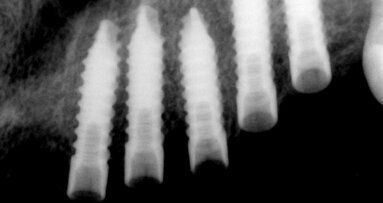

Zubní implantáty jsou skvělým přídavkem do repertoáru každého praktického zubního lékaře, jelikož nám umožňují nahradit ztracený zub bez ...